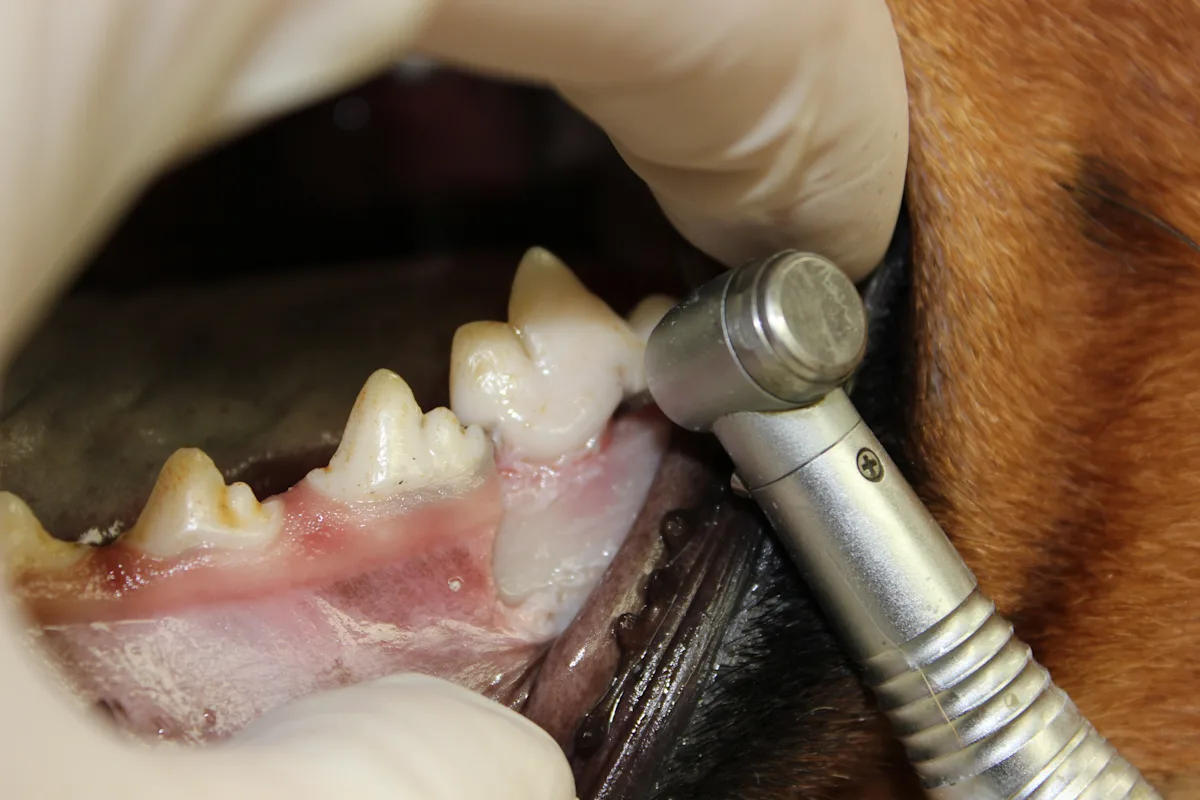

Step 10

Slightly free the alveolar mucosa from the lingual surface of the extraction site with the periosteal elevator. Place the periosteal elevator between the mucosa and alveolar bone while using a #8 round bur in a water-cooled high-speed handpiece to smooth the sharp edges from the alveolar bone (alveoloplasty). Palpate to ensure no sharp edges remain.

Remove debris from the alveoli with a surgical bone curette, and flush with sterile saline.